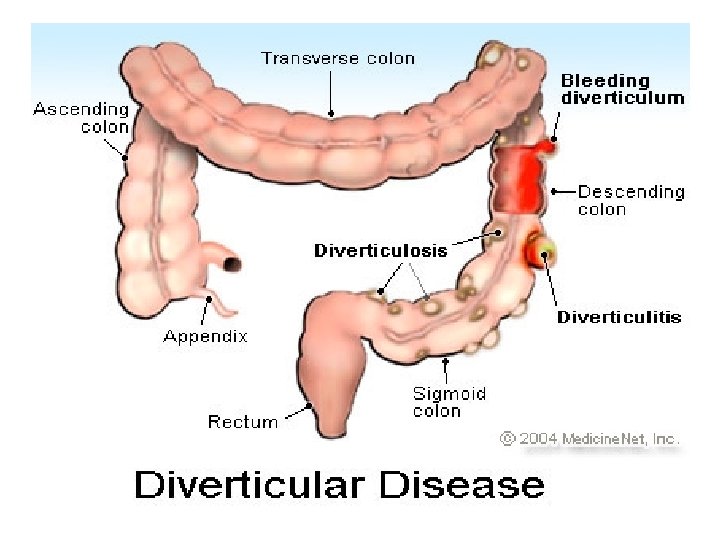

Diverticulosis • Diverticulosis is a condition in which the mucosa and muscularis mucosae herniate through the muscularis propria of the colon wall and produce a saccular outpouching. The major risk factor for developing diverticular disease is a low-fiber diet. The incidence increases with age, being rare before the age of 40 and affecting 50% of people over age 75. Only 10 -15% of patients will develop symptoms of the disease like pain, diarrhea, melena, or distention. Approximately 70% of diverticula occur in the sigmoid colon and 25% in the ascending colon. Most appear on the antimesenteric side of the colon, between taenia. Plain films and barium studies reveal diverticula as gas/barium-filled sacs parallel to the lumen of the colon. Most are 5 -10 mm in diameter, but may range from tiny spikes to 2 cm. The muscular layer may appear thickened with a distorted luminal contour in CT. Patients are managed with fiber supplements and stool softeners.